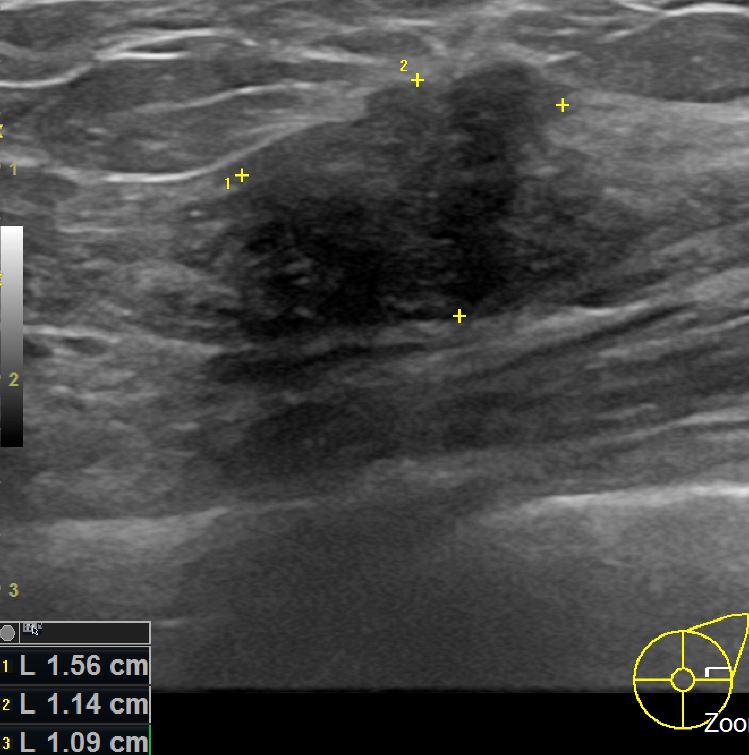

상기환자는 외부검사상 이상소견으로  내원하신 50대여성으로 좌상외측 의심스러운혹

조직검사후 유방암 진단되었읍니다